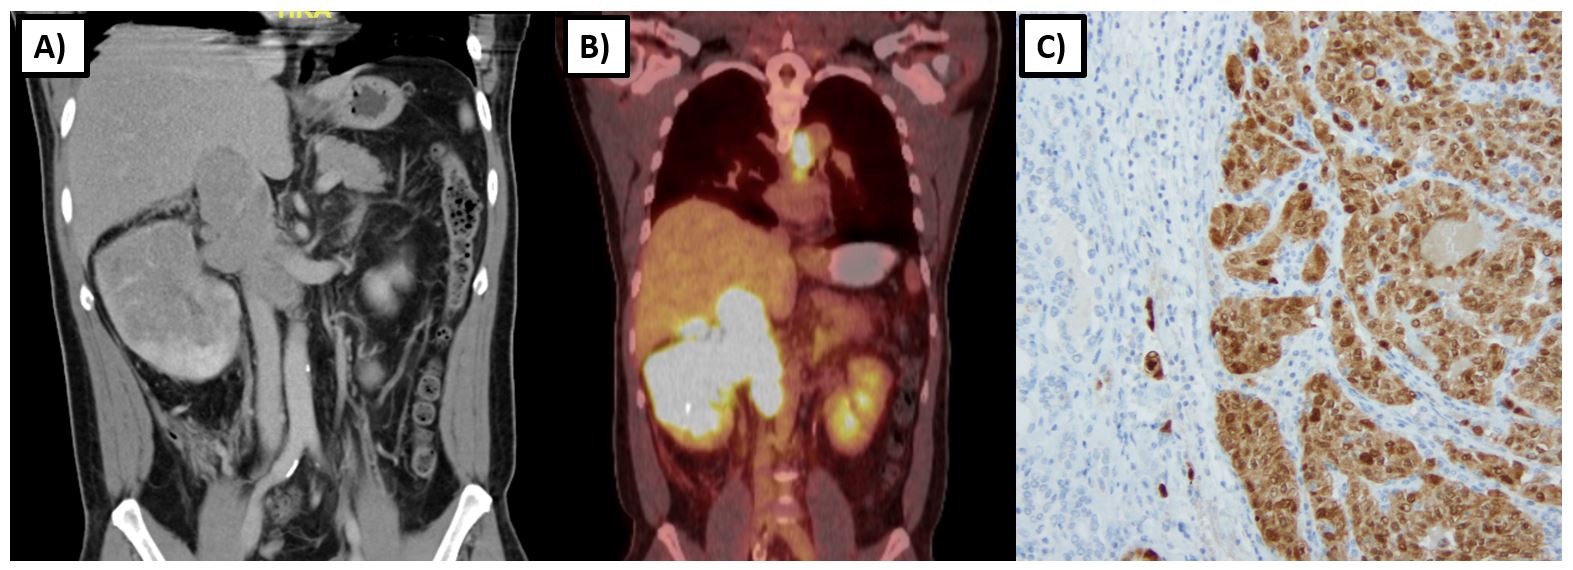

The FH gene encodes for the Krebs cycle enzyme fumarate hydratase, which catalyzes the conversion of fumarate to malate (Figure 1A). The loss of function in the FH gene leads to the autosomal dominant cancer syndrome known as HLRCC, which is characterized by cutaneous leiomyomas, early-onset and highly symptomatic uterine leiomyomas, adrenal macronodular hyperplasia, and a very aggressive form of kidney cancer now recognized as its own subtype – FH-deficient kidney cancer. This subtype can resemble papillary type 2, collecting duct, and tubulocystic RCC (Figure 2)13,14. The incidence and prevalence of HLRCC are currently unknown, but now several hundred families have been described in the literature. 15. The prevailing consensus was that HLRCC is quite rare, and among those with pathogenic FH mutations, the lifetime cumulative risk of RCC was 15-30%16,17. However with the widespread availability of panel testing that included the FH gene, many more patients are now being identified, leading to the belief that this condition is under- recognized. With large exome databases available, it is now evident that FH alterations are very common with carrier estimates between 1/1000 and 1/2500 individuals, suggesting a much lower RCC penetrance closer to 2-6%18.

Renal tumors in HLRCC tend to develop at an earlier age, with one series reporting a median age of onset of 37 years with a range of 10-773. Tumors tend to be unilateral and solitary with a particularly aggressive biological behavior compared to other types of hereditary kidney cancer. Imaging characteristics frequently demonstrate an infiltrative nature (>85%) with the invasion of the renal sinus fat (>80%) (Figure 2)19. Even smaller tumors have a propensity for early and rapid nodal and distant metastasis, as evidenced by one series in which four of seven patients with 2.0-6.7 cm T1 tumors had spread to regional lymph nodes or had distant metastases at the time of nephrectomy. 20 Another study found that among HLRCC patients with RCC, 47% (16/34) were metastatic at diagnosis, and another 35% (12/34) became metastatic within 3 years of diagnosis21.